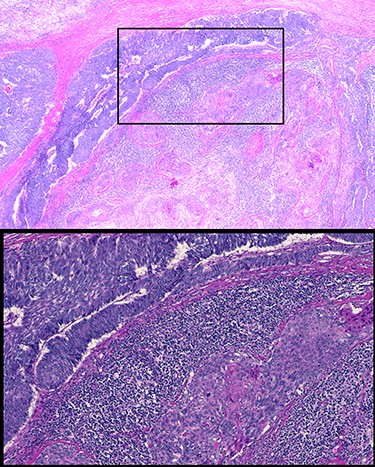

Patient’s post-operative course was notable for prolonged respiratory support due to phrenic nerve deficit. Patient’s respiratory failure resolved with 5-day course of intravenous antibiotics, spot diuresis and respiratory therapy. Patient was discharged home on post-operative day 10 day. Patient completed adjuvant radiation therapy at a total dose of 50 Gy in 25 fractions to the post-operative bed and anterior mediastinum. At 10-month follow-up, patient had no respiratory complaints with surveillance PET study showing no objective sign of tumor recurrence (Fig. 4).

Ten-month post-operative surveillance PET scan demonstrating no evidence of tumor recurrence.